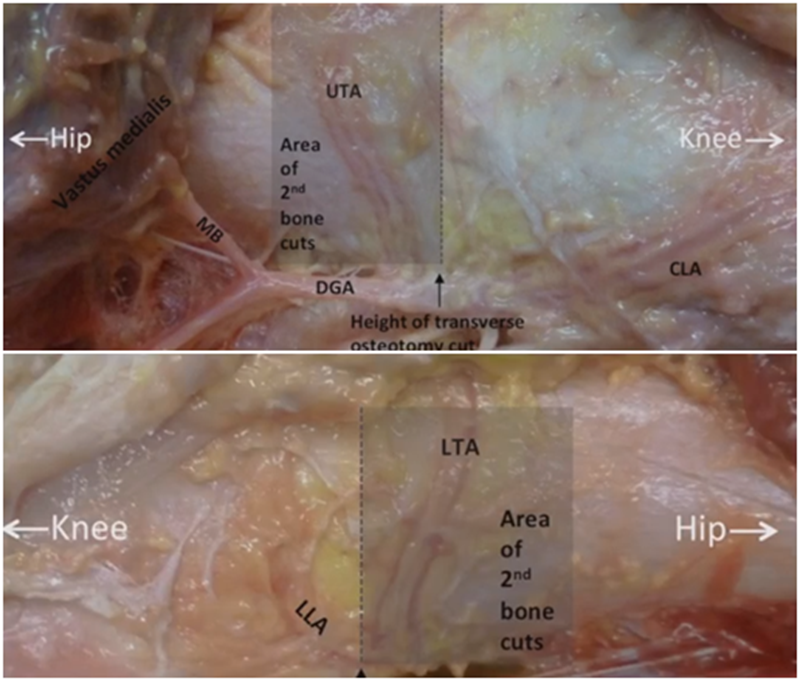

另一种为解剖标记法,在切开显露后可以看到一处恒定血管,即内侧上横动脉,在此附近做截骨即可。如做外侧闭合楔时,同样在外侧也可以看到一处恒定血管,为外侧横动脉。